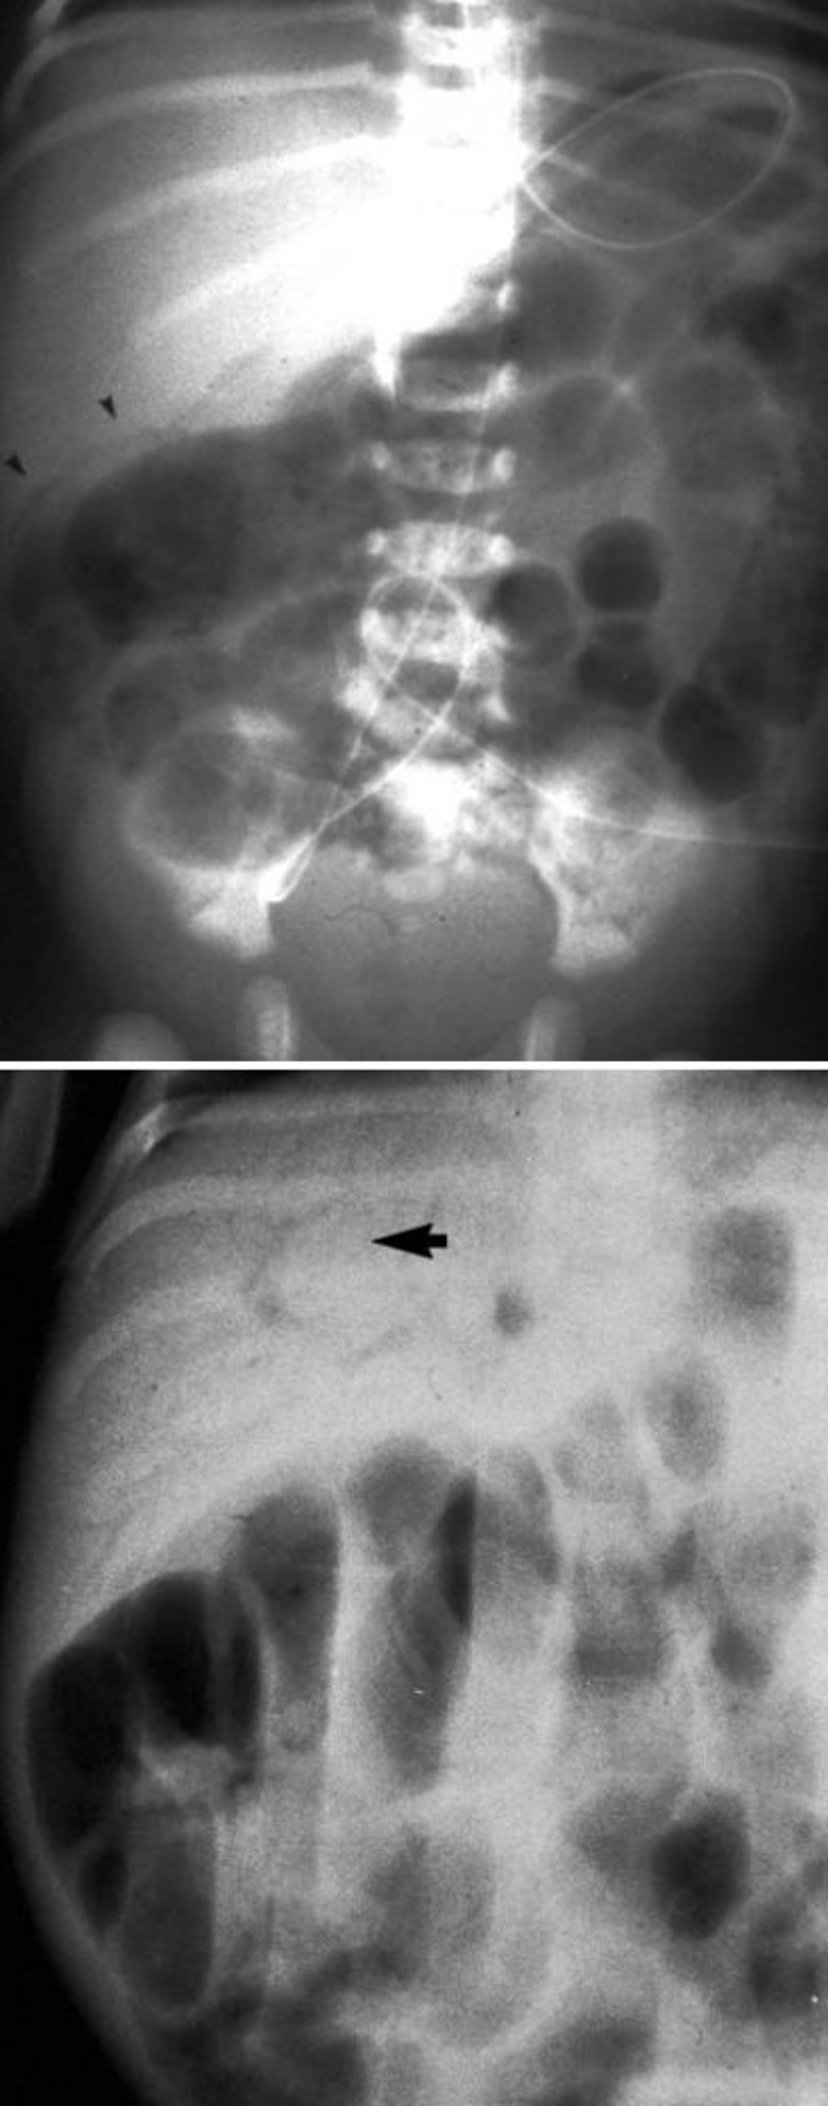

Caractéristiques radiologiques de l'entérocolite nécrosante

Cette image montre une pneumatose intestinale (en haut, pointes de flèches) et du gaz dans la veine porte (en bas, flèche).